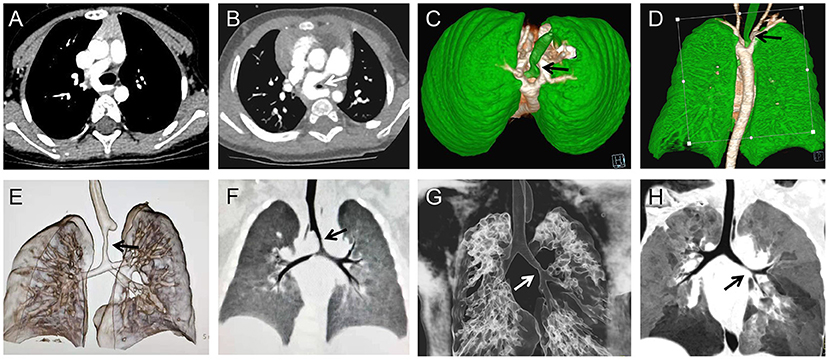

In the airway stenosis group, 20 were identified concomitantly with the diagnosis of their heart defect (17 ulmonary artery sling, 3 aortic ring) due to routine preoperative examination and 3 were identified subsequent to repair of their heart defects; compression stenosis of the left main bronchus was found by fiberoptic bronchoscopy in 4 cases. In the diaphragmatic dysfunction group, all cases were confirmed postoperatively by aside chest x-ray. In the pulmonary infection group, all cases had a history of multiple pediatric hospitalizations and underwent routine chest x-ray examination, and most of them were found to have pulmonary exudation; Twenty-two cases underwent lung CT examination before the surgery (Figure 1; Table 2).

Figure 1. Pulmonary CT and three-dimensional reconstruction of the airway, preoperatively showing the airway stenosis (arrows) was caused by pulmonary artery sling (A,B), double aortic arch (C,D), and a representative image of the stenosis (arrows) located in the trachea (E,F) and bronchus (G,H).

Narrow airways hinder the discharge of secretions, and increased secretions will increase airway resistance and increase the risk of lung infection. Therefore, trachea development should be carefully evaluated before surgery, and individualized measures, timely taken. However, the clinical manifestations of airway stenosis associated with congenital heart disease are easily masked by the symptoms of the primary heart disease, and preoperative confirmation of the diagnosis relies heavily on CT and bronchoscopy Very few cases were confirmed preoperatively, but most cases were not noticed until they could not be taken offline or repeated endotracheal intubation. In this study, 20 of the 23 cases in this group were found to have different degrees of tracheal or bronchial stenosis on preoperative CT examination. Presently, we preoperationally anticipate that patients may have airway stenoses, such as pulmonary sling, vascular ring, and enlargement of the left atrium. Usually, pulmonary CTA and three-dimensional reconstruction of the airway are performed to evaluate the degree of airway stenosis (Figure 1). Tracheal SLIDE anastomosis technique was performed during surgery (Figure 2), given preoperative CT evaluation (Figure 1) showed that the diameter of the stenotic site was <50% standard diameter for age. In this study, 7 children who had difficulty in weaning after cardiac surgery with severe tracheal stenosis were extubated within 3 weeks after tracheal slide surgery and recovered well. Given the preoperative CT results, stenotic tracheal sites ≥50% standard diameter for age can be treated selectively per patient and conditions by: (1) Prolonging the ventilation time; and (2) Tracheotomy techniques for airway management and step-down weaning exercises if the patient is on a ventilator for over 3 weeks. Significantly, in the absence of inherent tracheal stenosis, relative stenosis (trachea softening or collapse) is thus caused by enlarged blood vessels or cardiomegaly. However, if the malformation is not severe, a tracheal tube can be inserted through the narrow part to support the softened trachea for ~2 weeks. On the other hand, some cases can be treated by prolonging ventilator-assisted time; however, it might increase the risk of ventilator-associated pneumonia. If trachea collapse occurs following severe softening and is also challenging to gain recovery in a short time, a tracheal stent can be considered (Figure 3). Likewise, tracheal stents could also be considered for severe bronchomalacia collapse. If the trachea cannot be taken off the machine and a tracheal stent cannot be placed, we will consider tracheotomy after more than 3 weeks of mechanical ventilation.